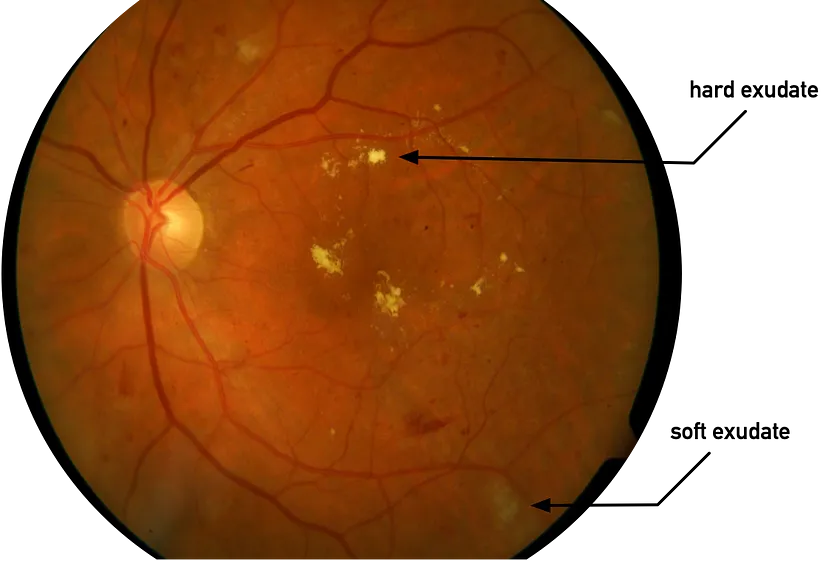

眼底镜检查图像上的硬性和软性渗出物, DIARETDB1 数据集

拉彭兰塔理工大学 Kauppi 等人的研究小组的 DIARETDB1 数据集包含 5 名健康志愿者和 84 名患有一定程度糖尿病视网膜病变的人的 89 张数字眼底镜检查图像,即眼底图像。糖尿病视网膜病变是糖尿病的一种并发症,会影响视网膜的小血管,长期血糖控制不足会导致血管损伤、微动脉瘤和渗出物,其中脂质(导致亮黄色硬渗出物)或血液(导致淡黄色、弥漫性软渗出物)积聚在眼底。接下来,我们将使用 GNG 来量化这些异常。DIARETDB1 数据集包含 ROI(感兴趣区域)蒙版,但这些蒙版仅勾勒出显示特定临床特征的区域。我们可以使用 Growing Neural Gas 来计算感兴趣区域中存在多少个硬渗出物簇吗?当然可以!

我们从一些图像处理开始,即细化感兴趣的区域。每张图像都由四位专家标记,从而创建了一个蒙版。我们可以对蒙版进行阈值处理,以要求一定数量的专家达成共识,这是带注释的研究图像中广泛使用的技巧(如果您不熟悉它,请滚动到底部!)。然后,我们使用硬性渗出液相对突出的亮黄色将它们转换为 GNG 可以开始表征的数据点(有关细节,请参阅配套笔记本,其中解释了一些额外的技巧,包括一些形态变换)。

接下来,我们利用脂质渗出液具有非常可识别的黄色这一事实,通过使用 OpenCV 的 inRange 函数对其进行阈值处理。此时,我们上面执行的 ROI 蒙版派上了用场,因为视神经盘(血管进入的亮黄色圆形结构,神经节神经元的轴突离开视网膜加入视神经)通常具有相似的颜色,具体取决于照明。使用 inRange 时,通常将图像转换为 HSV(色调、饱和度和明度)格式,因为这样可以更轻松地指定特定色调范围内的颜色。在 HSV 中,色调(“颜色”)占据颜色向量的单个元素(通常指定为色环上的度数),因此指定所有黄色就像指定黄色的近似色调角(大约 60°)并排除低饱和度(浅色,趋向于白色)或低明度(深色,趋向于黑色)边缘一样简单。对于 RGB 中的大多数颜色,这会复杂得多!幸运的是,OpenCV 及其 Python 绑定具有出色的颜色空间转换功能。